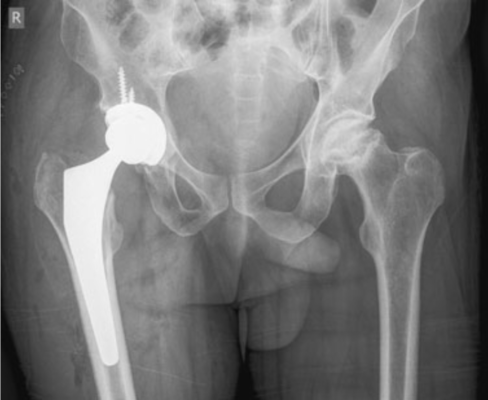

The man walks with a severe limp. Assessment of his hip abductors reveals a positive Trendelenburg sign on the left side. Measurement of the true leg lengths reveals a 1 cm shortening in the left leg compared to the right. Movement of the hip is painful but not significantly restricted. He has no obvious neurological or vascular deficit of the legs. A radiograph of this patient is shown in Fig. 3.1.

Bệnh nhân đi khập khiễng nhiều. Lượng giá các cơ dạng háng cho thấy dấu hiệu Trendelenburg dương tính ở phía bên trái. Đo chiều dài chân tuyệt đối phát hiện chân trái ngắn hơn chân phải 1 cm. Vận động khớp háng gây đau nhưng không bị hạn chế đáng kể. Bệnh nhân không bị khiếm khuyết mạch máu hoặc thần kinh rõ ràng ở chân. Hình chụp X quang của bệnh nhân này được thể hiện trong Hình 3.1.

Imaging the hip with anteroposterior and lateral views is the initial investigation. In early cases the radiographs may not reveal any signs of avascular necrosis. In late cases, subchondral sclerosis (increased density of the affected area, crescent sign), a thin subchondral fracture line in the necrotic segment, flattening of the femoral head, and collapse of the femoral head can be seen. The important differentiating point from advanced osteoarthritis is the preservation of joint space during the early stages of the disease.

Chụp x quang khớp háng thẳng và nghiêng là thăm dò bước đầu. Trong những trường hợp sớm, phim chụp X quang có thể không cho thấy bất kỳ dấu hiệu nào của hoại tử vô mạch. Trong những trường hợp muộn, có thể thấy đặc xương dưới sụn (tăng đậm độ vùng bị tổn thương, dấu hiệu lưỡi liềm), đường gãy xương mảnh dưới sụn ở đoạn hoại tử, dẹt chỏm xương đùi và xẹp/sụp chỏm xương đùi. Điểm phân biệt quan trọng với thoái hóa khớp giai đoạn nặng là sự bảo tồn khe khớp trong các giai đoạn đầu của bệnh.